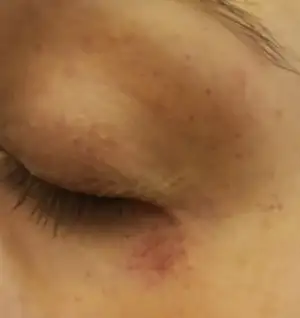

Gebelik lekesi mi deniyordu bunlara acaba?arkadaşım doğum yaptı yanaklarında ve alnında lekeler var ondan mı bilemedimKizlar iki gozumun etrafinda birden boyle kirmizi noktalar cikti. Kasinti ya da herhangi birsey yok. Fikri olan var midir?

Gebelik lekesi kahverengi olur diye biliyorum. Benimki bildigin kirmizi. Sadece goz cevremde, goz kapagimda var baska bi yerde yok, endiselendim..Gebelik lekesi mi deniyordu bunlara acaba?arkadaşım doğum yaptı yanaklarında ve alnında lekeler var ondan mı bilemedim

Kasinti agri falan yok yazmissiniz sanirim bence endiselenicek bi durum yoktur gozunuzj ovmayla bile olabilir sabahaha bisi kalmaz insallahGebelik lekesi kahverengi olur diye biliyorum. Benimki bildigin kirmizi. Sadece goz cevremde, goz kapagimda var baska bi yerde yok, endiselendim..

İnşallah kötü birşey değildir yediğin birşey de dokunmuş olabilir.sabaha geçer belkiGebelik lekesi kahverengi olur diye biliyorum. Benimki bildigin kirmizi. Sadece goz cevremde, goz kapagimda var baska bi yerde yok, endiselendim..